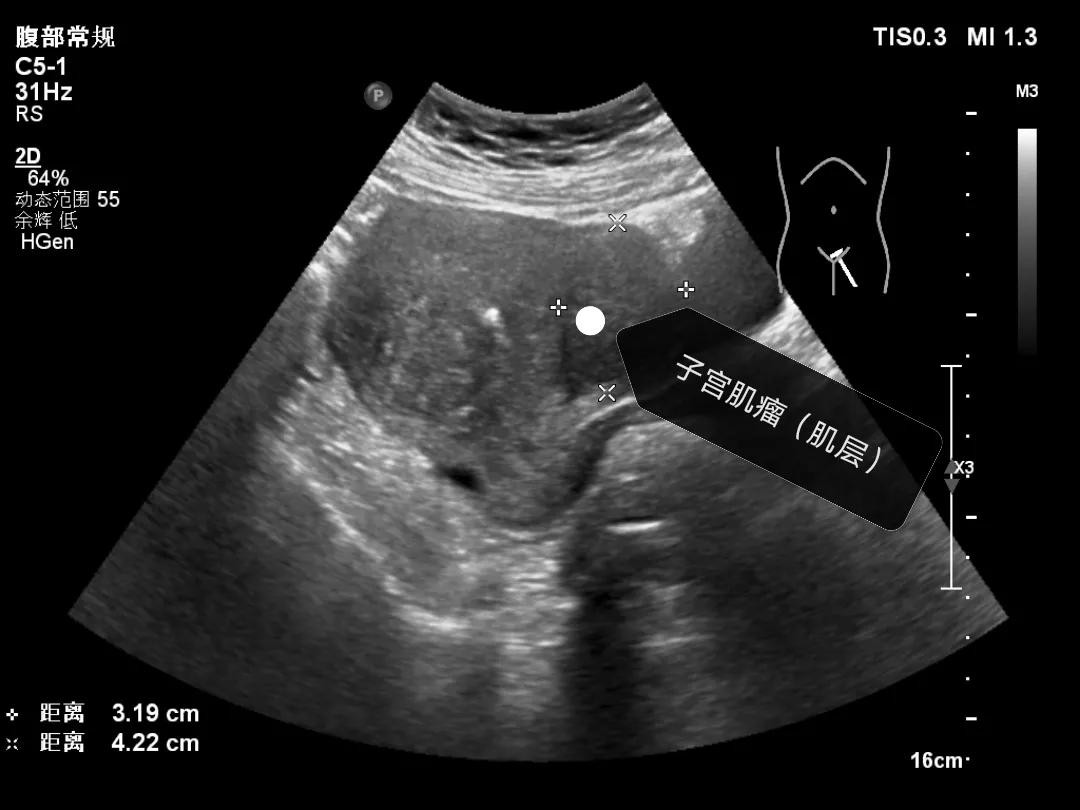

女性朋友关心的第二个问题“怎么确定自己有没有子宫肌瘤、肌瘤多大”,确定是不是患有子宫肌瘤很简单,做一个超声检查就可以了,下面我给大家分享一下子宫肌瘤的超声表现,子宫肌瘤根据位置分为粘膜下肌瘤、肌壁间肌瘤和浆膜层肌瘤,在超声上主要表现为低回声结节,边界比较清楚,小的肌瘤一般形态规则,呈椭圆形,大的肌瘤形态可表现为欠规则,呈分叶状,肌瘤周边一般可见环状的血流信号。

肌壁间肌瘤